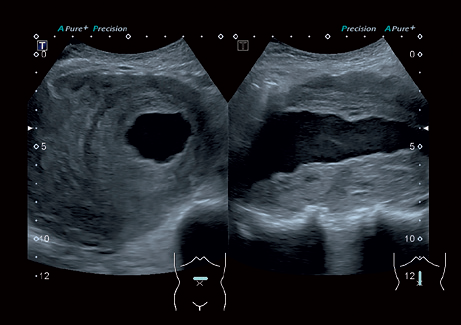

• ApliPure - технология повышения качества изображения

• Precision Imaging - технология получения изображений мелких деталей с четко очерченными границами и высокой однородностью

• Глубина сканирования: 40 см;

• Увеличение изображение: в 27 раз;

• Динамический диапазон: 216 Дб;